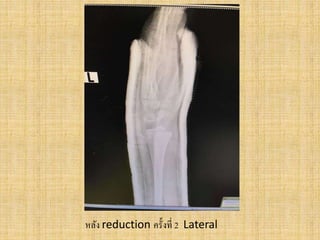

หลัง reduction ครั้งที่ 2 Lateral

Film Left wristAP ,หลังใส่ slab ก่อนทาการผ่าตัด

Film Left wristoblique , หลังใส่ slab ก่อนทาการผ่าตัด